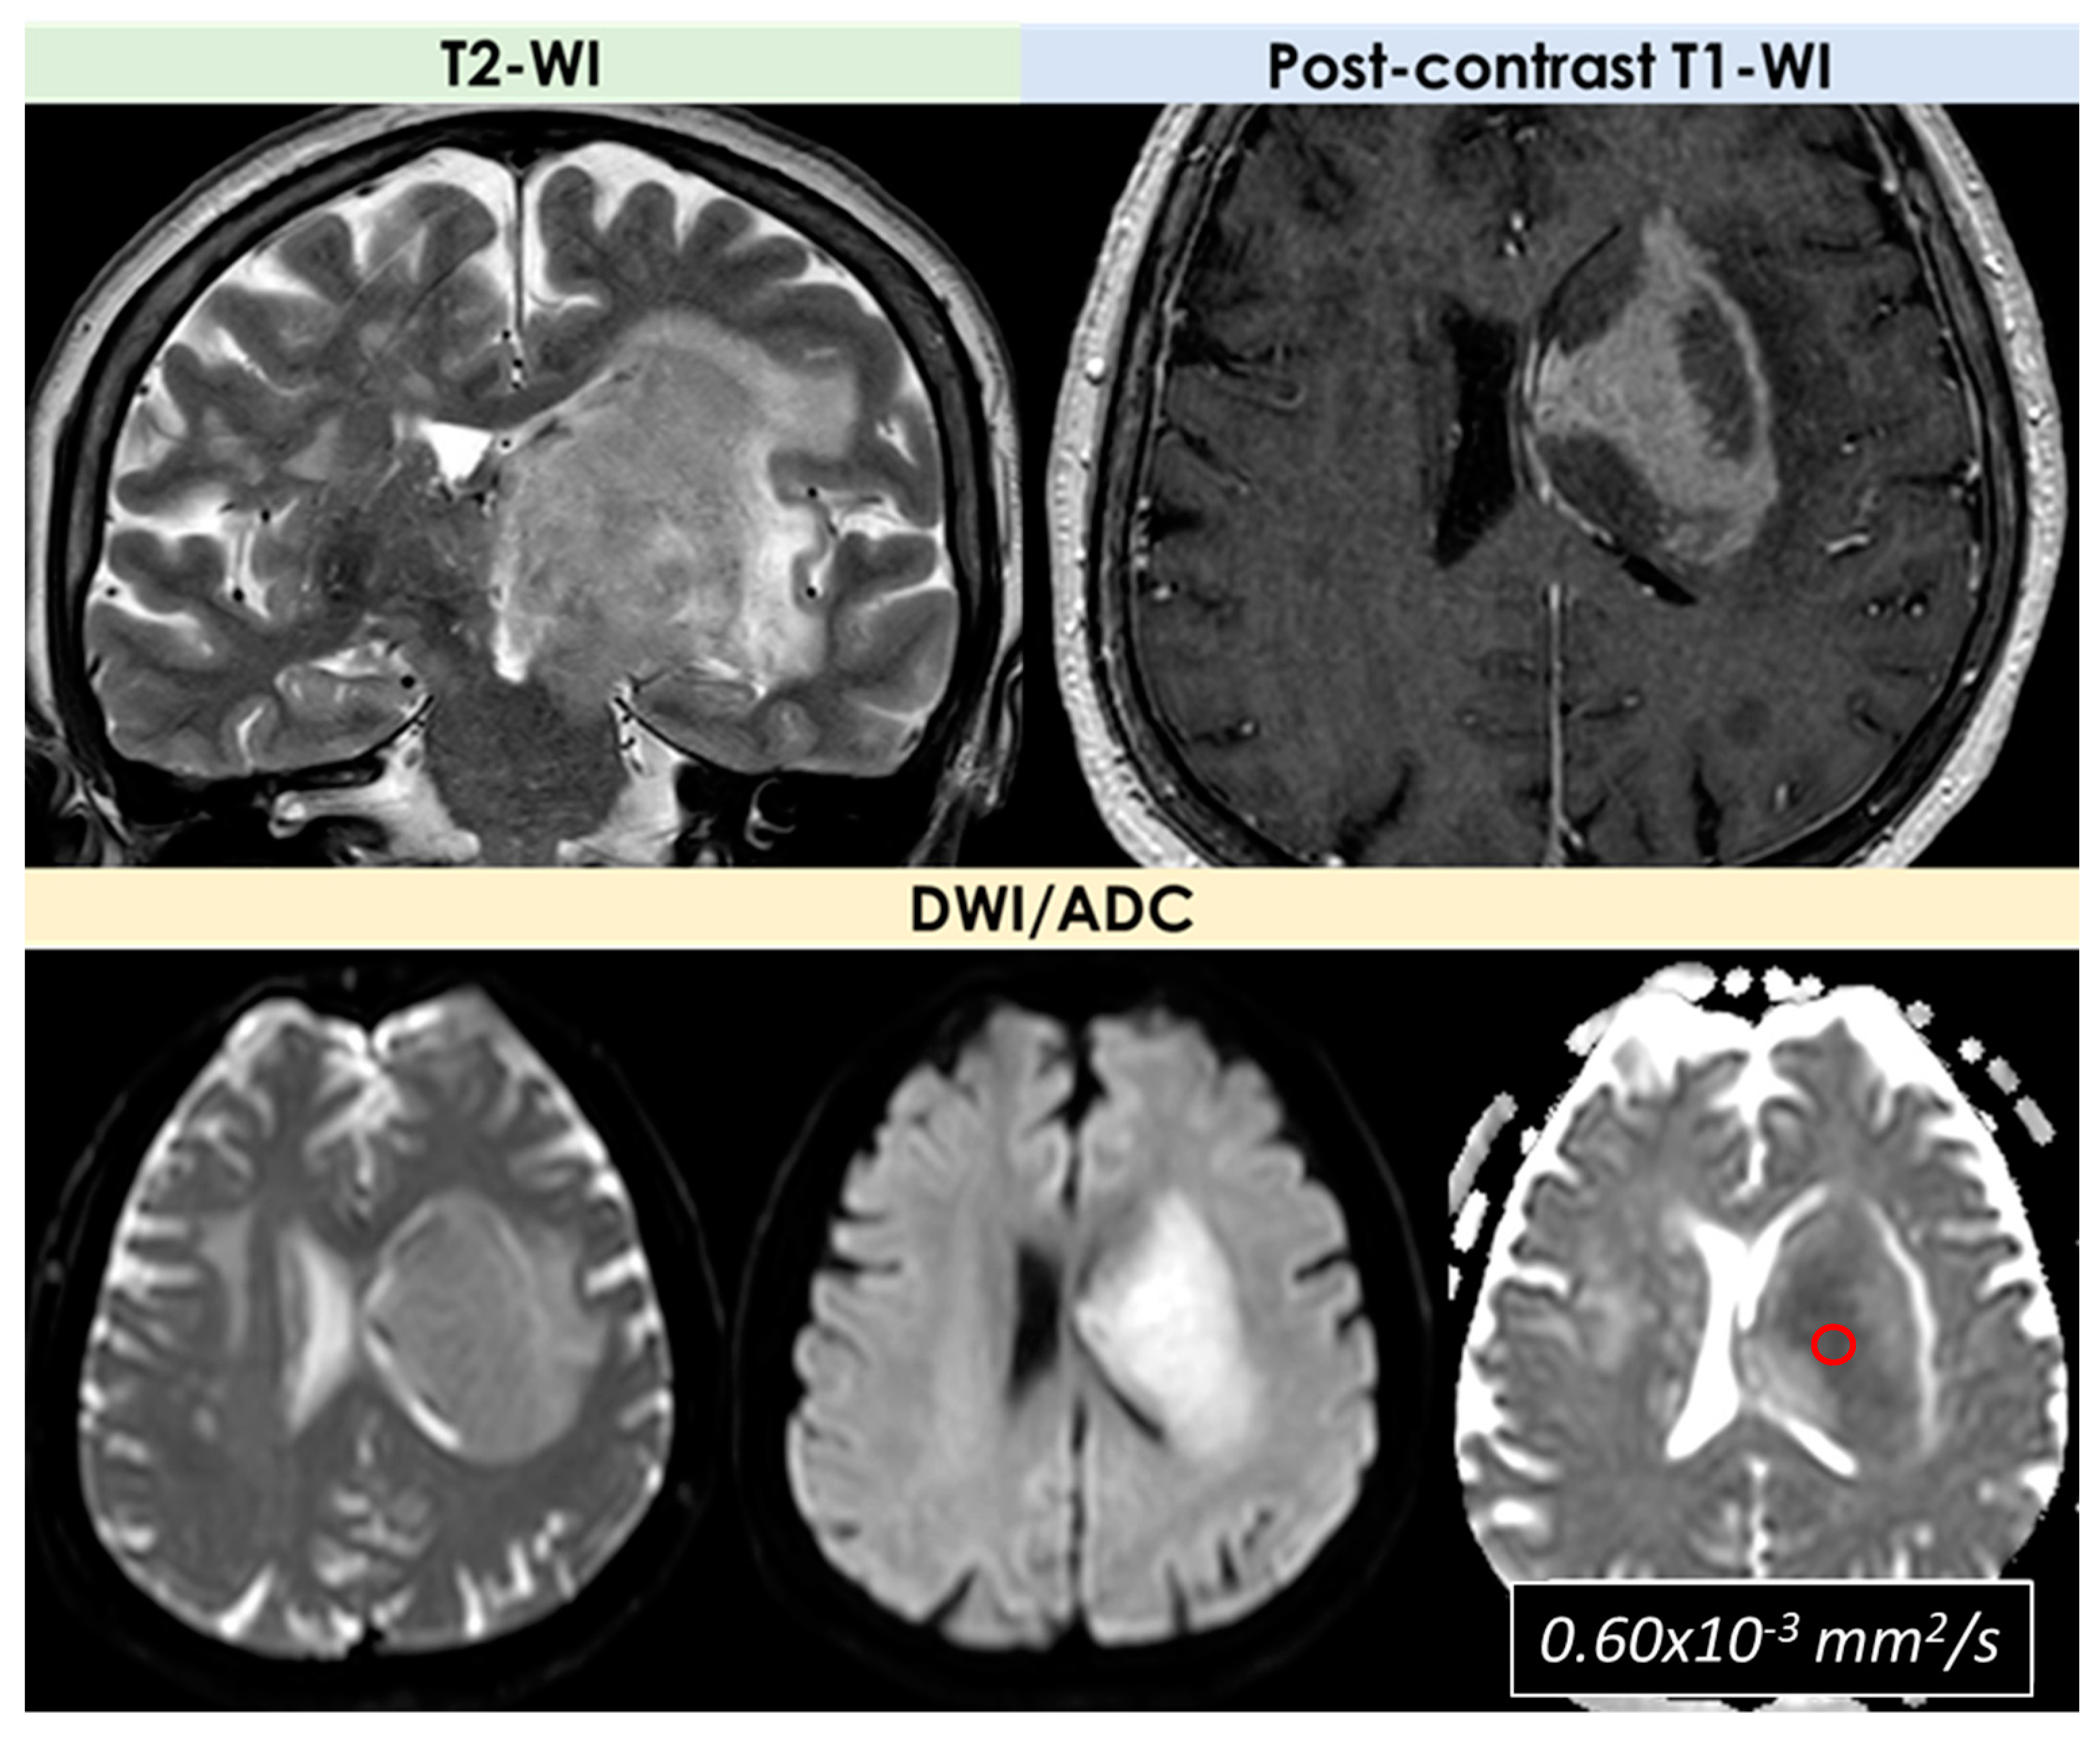

3.2. Primary Central Nervous System Lymphoma

| DWI/ADC | Hyperintense on DWI/hypointense on ADC maps Decreased FA values in lesions | High ADC values in center of lesion and relatively low ADC values in periphery of lesion Threshold for the minimum ADC value for distinguishing TDLs from PCNSL is 0.556 × 10−3 mm2/s | Hypointense in DWI and ADC | Hypointense on DWI and ADC | “Eccentric target sign” consisting of an eccentric nodule along the rim of an enhancing lesion on T1-WI ADC > 1.6 × 10−3 mm2/s suggestive of toxoplasmosis |

| DSC-MRI | rCBV lower than HGG Characteristic TIC | Few data with variable findings | rCBV usually higher than PCNSL, but variable findings | No data | rCBV lower than that in necrotic glioblastomas and metastases |

| Spectroscopy | Elevated lipid peaks and high Cho/Cr ratios | Increased Cho- peak Decreased NAA peak Increased Cho/NAA ratio | Elevated lipid peaks High Cho/Cr ratio | No data | No data |